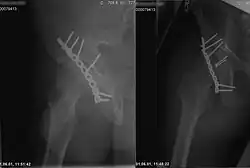

Mit Röntgenstrahlung kann der menschliche Körper durchleuchtet werden, wobei vor allem Knochen, aber bei modernen Geräten auch innere Organe sichtbar werden (siehe auch Röntgen). Dabei wird ausgenutzt, dass das in den Knochen vorkommende Element Calcium mit Z = 20 eine deutlich höhere Ordnungszahl hat als die Elemente, aus denen die weichen Gewebe hauptsächlich bestehen, nämlich Wasserstoff (Z = 1), Kohlenstoff (Z = 6), Stickstoff (Z = 7) und Sauerstoff (Z = 8). Zudem werden Röntgenkontrastmittel eingesetzt, die meist Iod (Z = 53) oder Barium (Z = 56) enthalten. Neben herkömmlichen Geräten, die eine zweidimensionale Projektion produzieren, werden auch Computertomographen eingesetzt, die eine räumliche Rekonstruktion des Körperinneren ermöglichen.